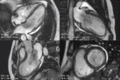

تصوير القلب بالرنين المغناطيسي

تصوير القلب بالرنين المغناطيسي هو تقنية تصوير طبية غير غازية (لا تدخل للجسم) لتقييم وظيفة وهيكل الجهاز القلبي الوعائي. وهذه التقنية مشتقة من ومستندة إلى نفس المبادئ الأساسية للتصوير بالرنين المغناطيسي ولكن مع التعديل من أجل الاستخدام في نظام القلب والأوعية الدموية.[1][2]